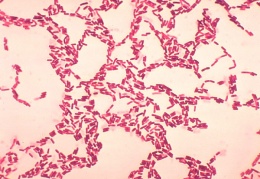

Bacillus coagulans

Concepto:Es un tipo de bacterias. Se utiliza como bacterias "beneficiosas" de manera similar al Lactobacillus y otros probióticos.